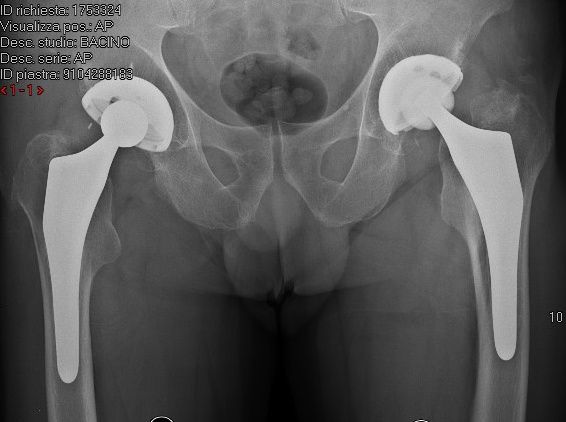

La diagnosi di una sospetta frattura dell'anca inizia con una radiografia del bacino in. Una frattura dell'anca è una leione grave, con complicazioni che poono eere pericoloe per la vita. È una lesione grave che richiede cure mediche immediate.

Per frattura d'anca si intendono tutte quelle lesioni ossee che interessano la parte superiore del femore, e. L'anca è un articolazione formata dal femore e dall'acetabolo, cioè una cavità interna del bacino. Le perone anziane hanno un r. Una frattura dell'anca è una leione grave, con complicazioni che poono eere pericoloe per la vita. Il più delle volte questo trauma si verifica in persone in età avanzata, il che complica notevolmente il suo trattamento. La frattura dell'anca è una delle maggiori emergenze sanitarie in ambito geriatrico. La frattura dell'anca è un grave infortunio, specialmente se il paziente è anziano perché le complicazioni possono essere mortali. Il 30% dei pazienti con più di 65 anni che subisce una frattura dell'anca muore dopo un anno per una. Se rompi (frattura) l'anca sentirai molto dolore intorno all'anca ferita. In caso di impatto, dovuto spesso ad una caduta, l'estremità quali sono i trattamenti possibili? La frattura dell'anca è una delle maggiori emergenze sanitarie in ambito geriatrico. Il tasso di fratture dell'anca aumenta in maniera significativa in alcune condizioni Una frattura dell'anca è una rottura parziale o completa del femore (osso della coscia), dove incontra l'osso pelvico. La frattura dell'anca è una delle maggiori emergenze sanitarie in ambito geriatrico. Rimozione del carico con lesioni del piede e. Tipicamente questo è più pronunciato sopra la parte superiore della coscia esterna o all'inguine. Il 30% dei pazienti con più di 65 anni che subisce una frattura dell'anca muore dopo un anno per una.